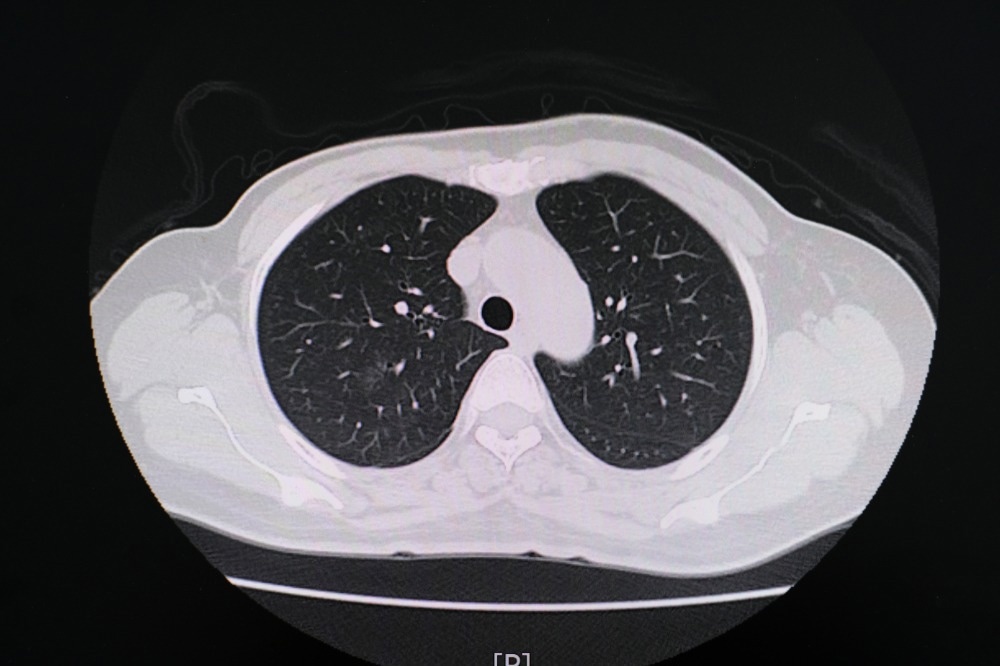

Study: Chest CT Findings in Marijuana Smokers. Image Credit: PIJITRA PHOMKHAM / Shutterstock.com

In a recent Radiology journal study, researchers report chest computed tomography (CT) findings that the lungs of marijuana smokers exhibit more significant levels of airway inflammatory markers and emphysema as compared to those of tobacco-only smokers.

As compared to non-smokers, the CT findings for marijuana smokers indicated different rates of emphysema, bronchial thickening, bronchiectasis, mucoid impaction, and centrilobular nodules, all of which are CT markers for airway inflammation. Gynecomastia was also reported in 38% of marijuana patients as compared to 16% of non-smokers.

Upon comparison of CT findings between marijuana and tobacco-only smokers, the researchers reported differences in bronchial thickening, bronchiectasis, and mucoid impaction. Furthermore, higher rates of emphysema were observed in age-matched marijuana smokers as compared to tobacco-only smokers of 93% and 67%, respectively. No differences were observed when comparing the occurrence of centrilobular nodules between marijuana and tobacco-only smokers; however, this may be due to the high rate of tobacco smokers who also smoked marijuana.

Paraseptal emphysema was also more frequently identified in marijuana smokers as compared to the lungs of tobacco-only smokers. Conversely, centrilobular emphysema was primarily visualized in the lungs of tobacco-only smokers.